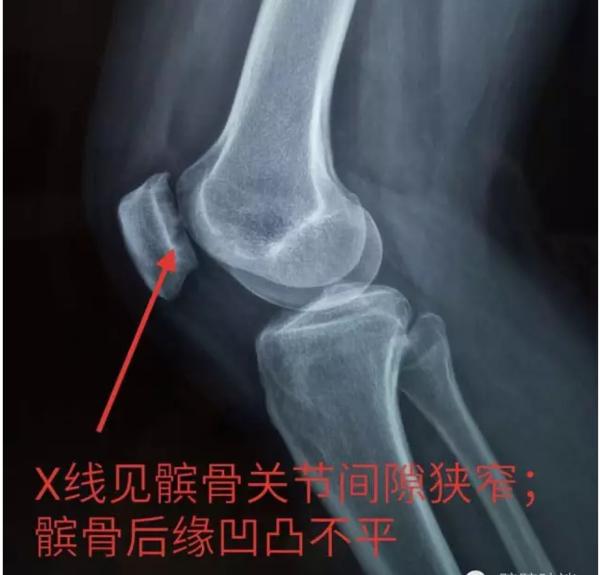

查膝关节X线示:

诊断:髌骨软化症